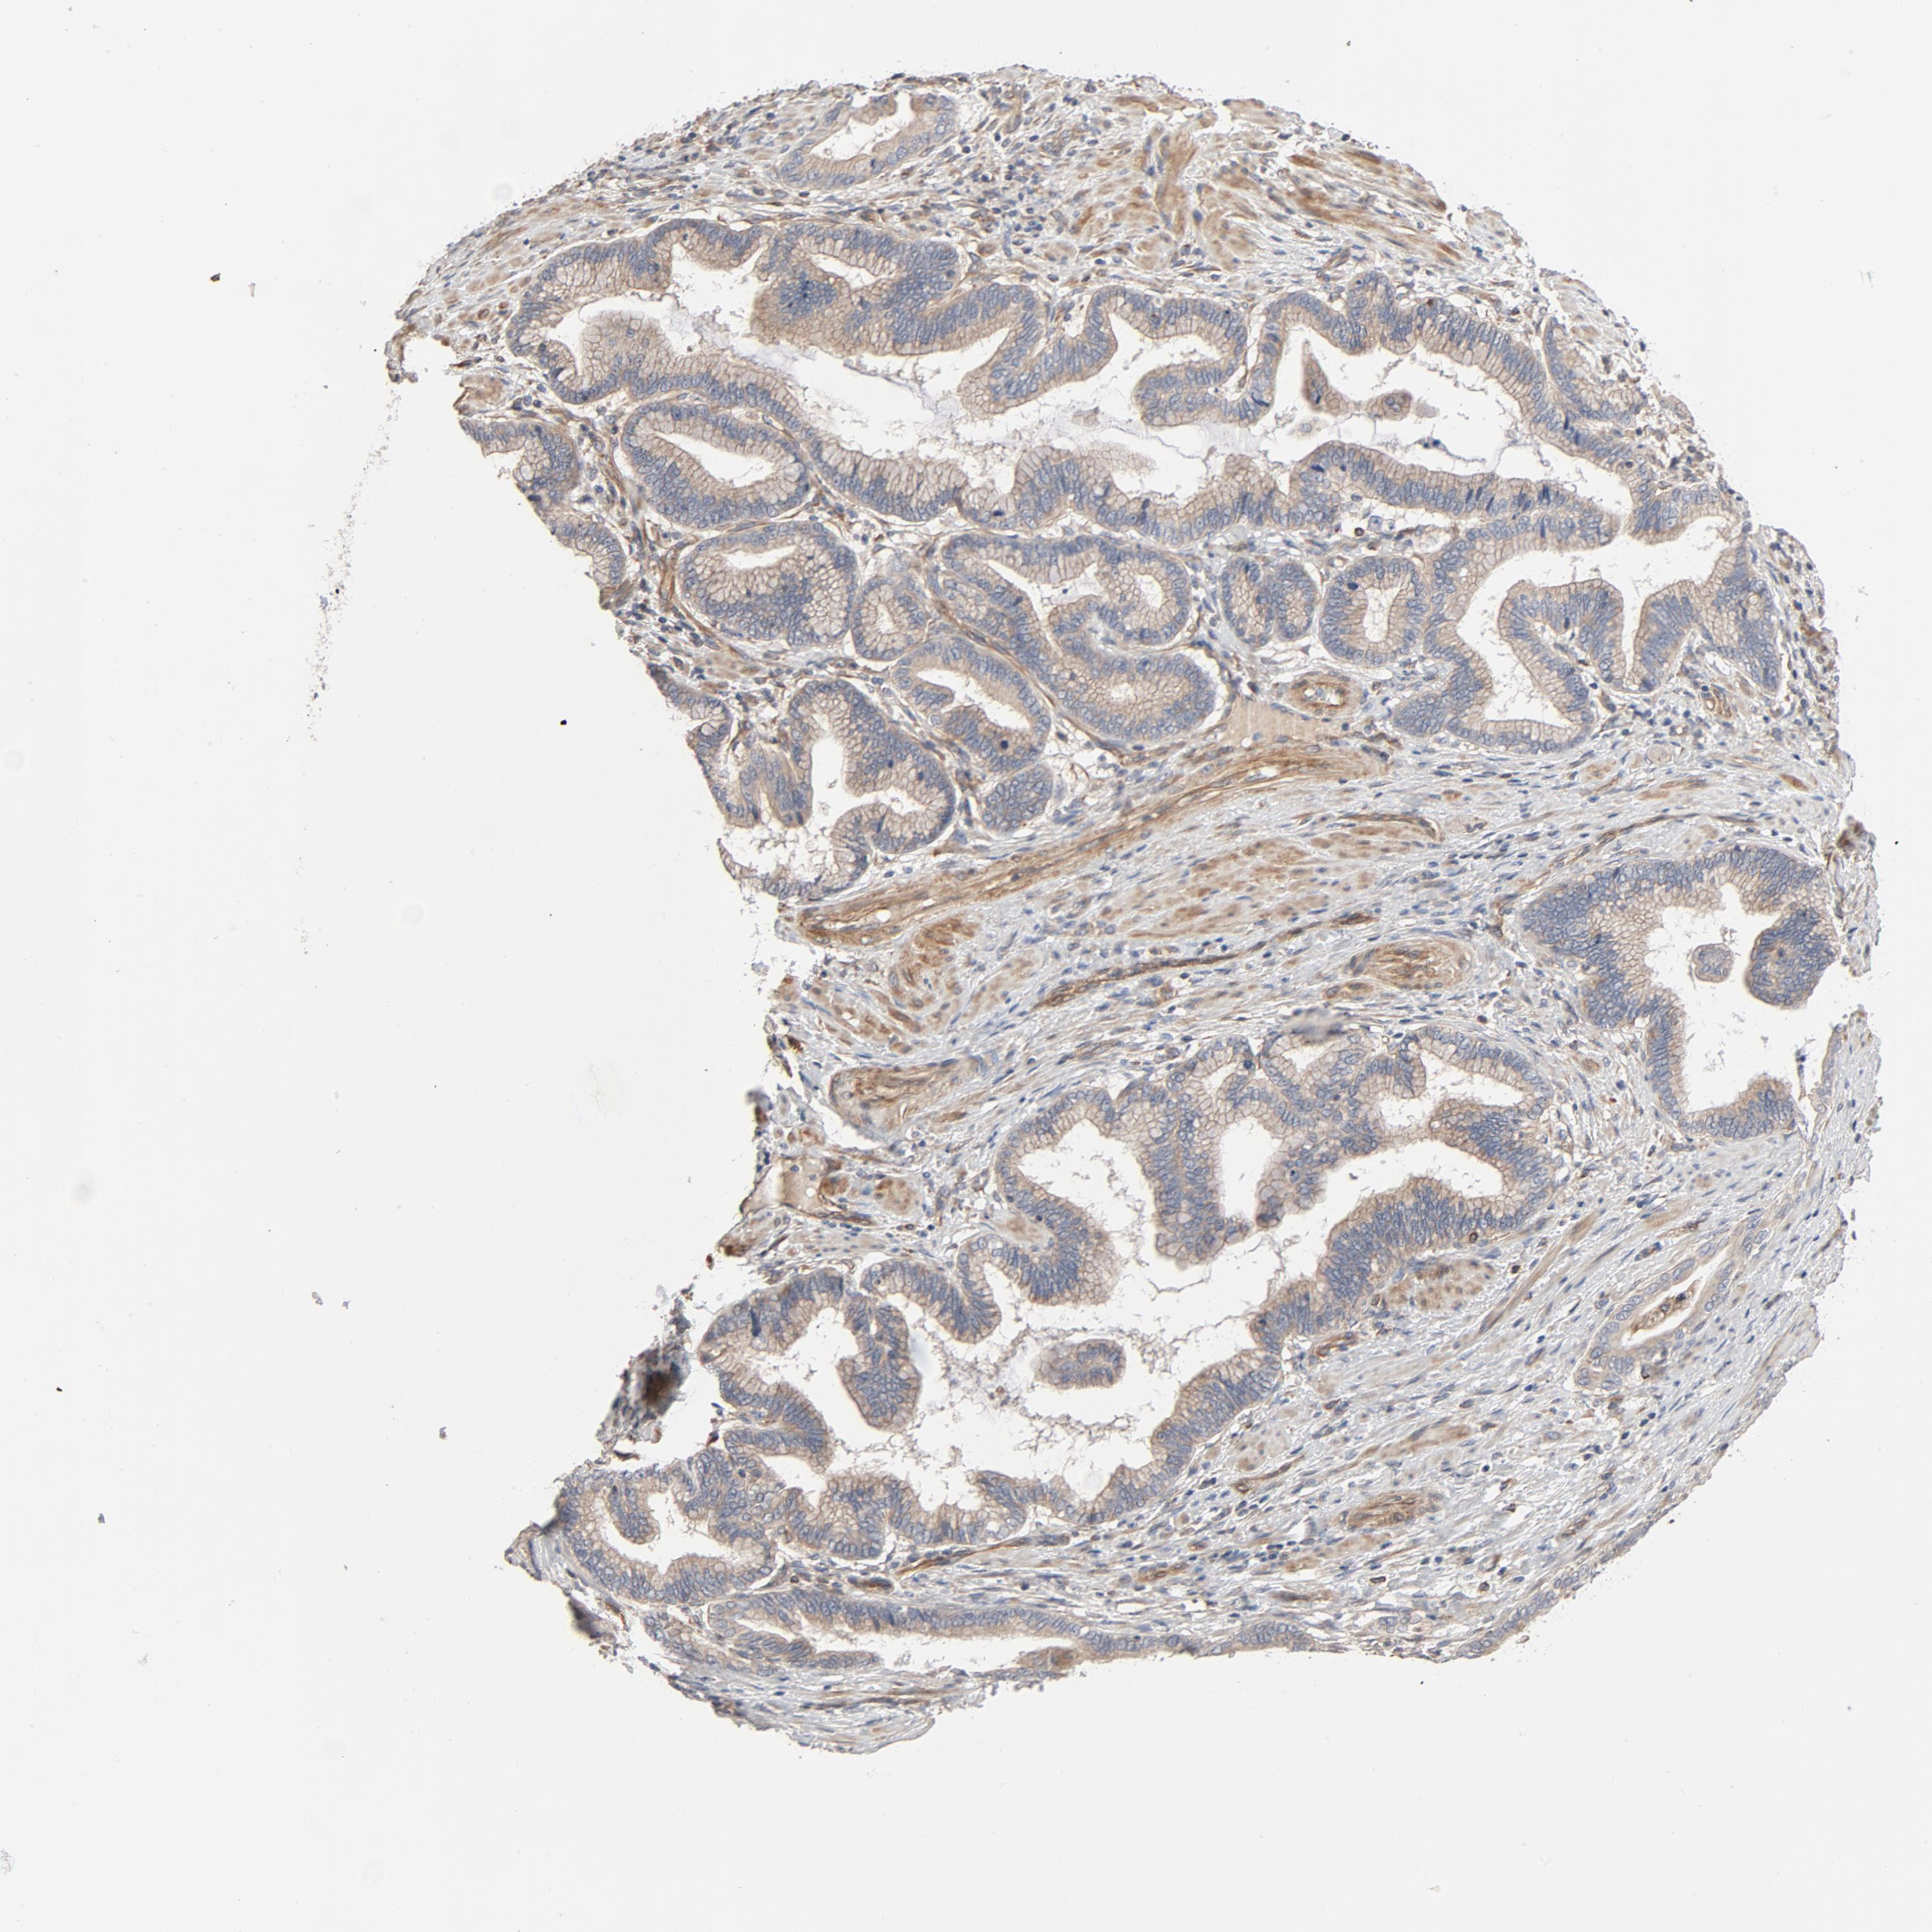

PANCREATIC CANCER - Protein expressioni

A mouse-over function shows sample information and annotation data. Click on an image to view it in a full screen mode. Samples can be filtered based on level of antibody staining by selecting one or several of the following categories: high, medium, low and not detected. The assay and annotation is described here.

Note that samples used for immunohistochemistry by the Human Protein Atlas do not correspond to samples in the TCGA dataset.

Antibody stainingi

Antibody staining in the annotated cell types in the current human tissue is reported as not detected, low, medium, or high, based on conventional immunohistochemistry profiling in selected tissues. This score is based on the combination of the staining intensity and fraction of stained cells.

Each image is clickable and will lead to virtual microscopy that enables deeper exploration of all samples and also displays staining intensity scores, fraction scores and subcellular localization as well as patient and tissue information for each sample.

Antibody HPA003747

Antibody HPA019769

Adenocarcinoma, NOS

Adenocarcinoma, metastatic, NOS